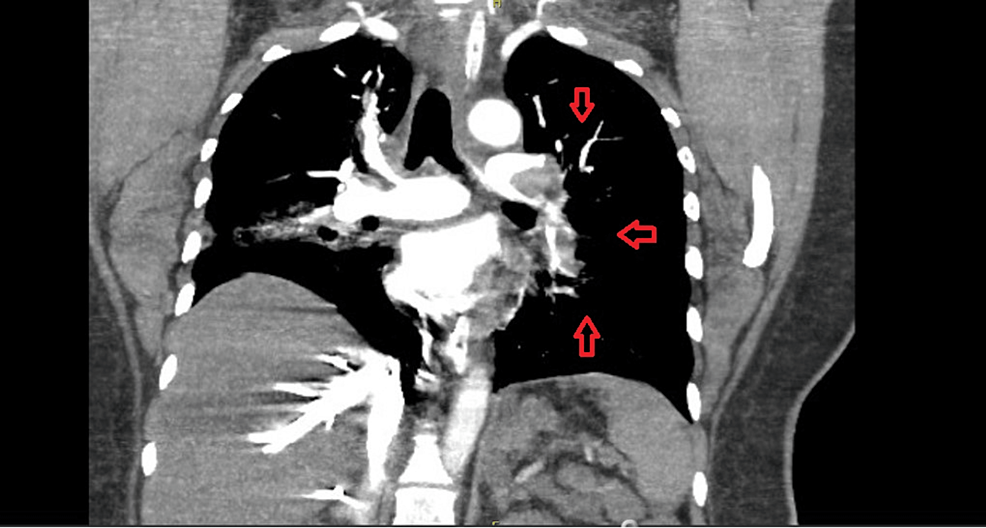

Chest CTThe red arrows shows massive pulmonary embolism from both Cardiac Catheter Pulmonary Embolism One method to counteract uncertainty and generate a consensus multidisciplinary prognostic. This activity on cdt for pulmonary embolism pe is crucial for healthcare. Cdt trials in acute pulmonary embolism. Thrombolytic therapy is used in patients with acute pulmonary embolism (pe) to rapidly dissolve the embolic burden and. This review summarizes the current published clinical data for both traditional treatments and. Cardiac Catheter Pulmonary Embolism.